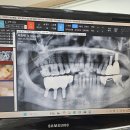

임플란트시술과정에서 2024.09.28해당카페글 미리보기

어금니발치후 쇠기둥? 을 심었고 담달에 본뜰예정이었는데 오늘 당황스럽게도 쇠기둥?이 쏙 빠졌습니다. 이럴수도 있나요? 아프다거나 뭐 그런건아닌데. 걱정이됩니다 ㅜㅜ 새롭게 다시시작해야하는건지 월요일치과다시갈건데 무서워요ㅜㅜ